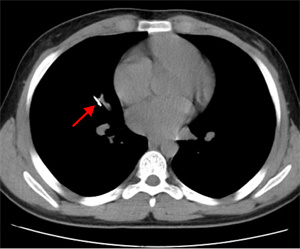

10月18日夜间急诊,来了一位14岁小患者,他在将手表零件放口中玩耍时,不慎吸入气管内。气管内异物是十分危急的,随时可能危及生命。小患者自觉胸闷不适,不时有咳嗽。急诊胸片和CT可以清晰地显示位于右中叶内侧段一长约2.3cm针形异物,两端较尖,急诊科医生程争启紧急联系呼吸与危重症医学科会诊,白克林主任考虑金属异物锐利可能损伤肺内血管造成大出血,准备急诊行内镜取异物。疼痛科、内镜室医务人员迅速反应,立即从家中赶往医院,争分夺秒做好各种术前准备工作。

白主任还邀请消化内科副主任吴斌、胸外科许涛医生一同到场,齐心协力保障患儿。然而,白主任用支气管镜反复多次查找,却始终没有发现异物,同时使用小探头超声内镜扫描,也一无所获。考虑有移位可能,白主任果断建议床旁摄片,进行气管镜下定位。时间紧迫,影像科技师汪津立刻带着机器来到气管镜室。经过摄片,发现金属异物显影在了胃泡里!